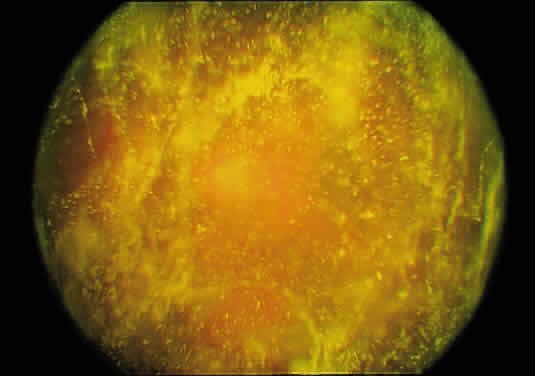

During aging, there are substantial rheologic, biochemical, and structural alterations in vitreous.12,95The ensemble of these changes can be appropriately referred to as age-related vitreous degeneration (ARVD).

RHEOLOGIC CHANGES

Rheology is a term that refers to the gel–liquid state of the vitreous. After the age of 45 to 50 years, there is a significant decrease in the gel volume and an increase in the liquid volume of human vitreous. Postmortem studies of dissected vitreous qualitatively confirmed these findings and determined that liquefaction begins in the central vitreous.5,12 This finding supports the observation that the central vitreous is where fibers first appear (Fig. 12) and is consistent with the concept that breakdown of the normal collagen-HA association results in the simultaneous formation of liquid vitreous and aggregation of collagen fibrils into bundles of parallel fibrils seen as large fibers.7,8,12 In the posterior vitreous, pockets of liquid vitreous are formed, recognized clinically as lacunae (Fig. 22). When a single large pocket forms, the terms bursa or precortical pocket are used.6,9 As previously mentioned, the large lacuna is a manifestation of age-related liquefaction, or synchisis, and does not represent an anatomic entity.10,11 Flood and Balazs154 found evidence of liquid vitreous after the age of 4 years and observed that by the time the human eye reaches adult size (age 14 to 18 years), 20% of the total vitreous volume consists of liquid vitreous (Fig. 23). In these postmortem studies of fresh unfixed human eyes, it was noted that after the age of 40 years, there is a steady increase in liquid vitreous. This occurs simultaneously with a decrease in gel volume. By the ages of 80 to 90 years, more than half of the vitreous is liquid.

Fig. 22. Human vitreous structure in old age. The central vitreous has thickened, tortuous fibers. The peripheral vitreous has regions devoid of any structure, which contain liquid vitreous. These regions correspond to lacunae, (arrows) as seen clinically with biomicroscopy.